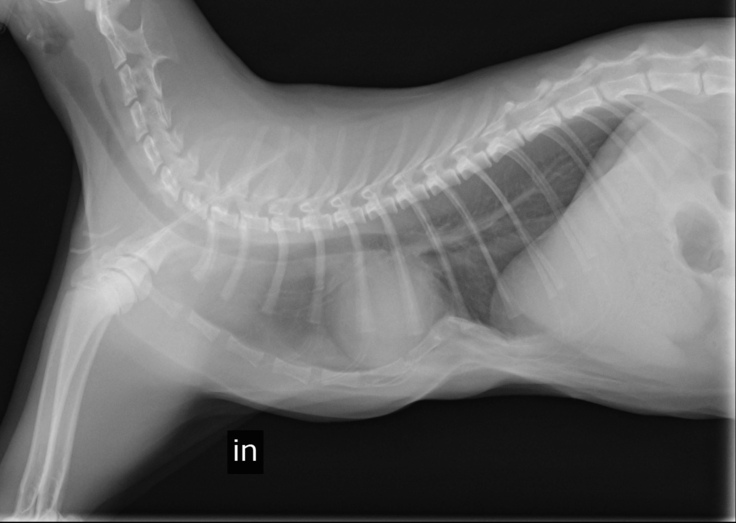

これはプレートを除去し胸骨の矯正が完了した際の写真です。

呼吸もしやすくなり日々元気にすくすく成長しています。